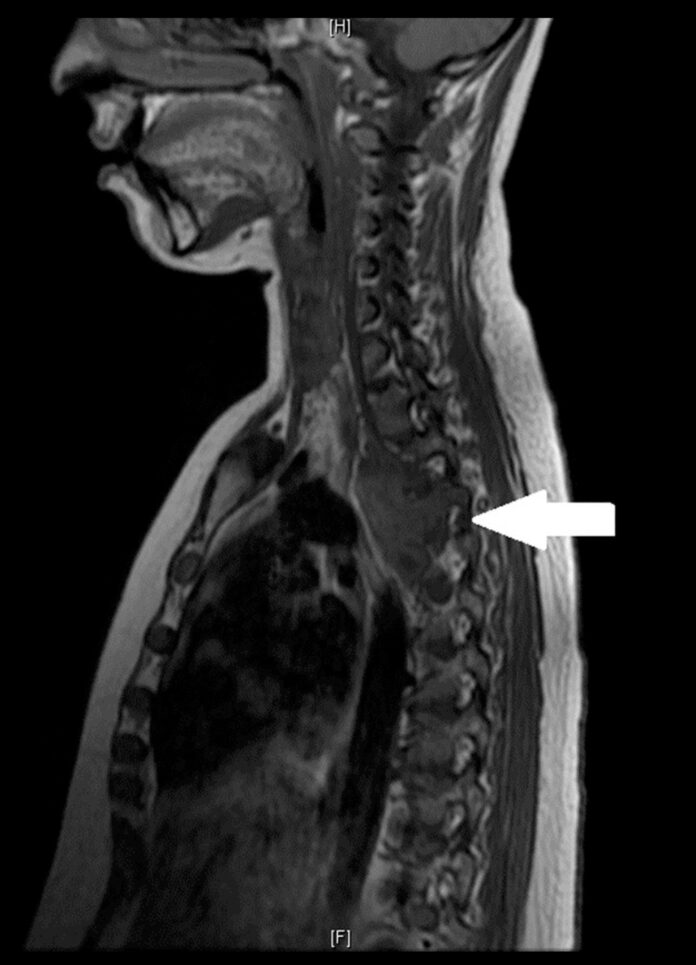

from radiopaedia.org

Pott's disease, MRI Stock Image M240/0490 Science Photo Library Is Pott's Disease Fatal Spinal tuberculosis that isn't treated can be fatal. The manifestations depend upon the duration of illness, severity of the disease, site of the lesion, and presence of associated complications including deformity and neurological deficit. Unfortunately, diagnosis of spinal tb is often delayed until the spine is deformed. Deformity and motor deficit are the most serious consequences of pott disease and. Is Pott's Disease Fatal.